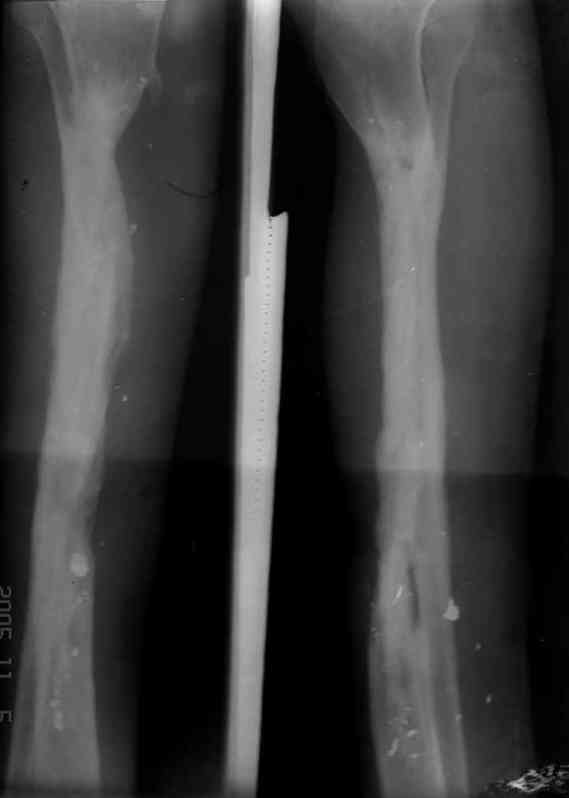

Реализовал описанную выше методику, и в итоге вот что получилось. Высылаю лишь прямые проекции,

в боковых тоже всё в тему.

Очень пригодились карбоновые кольца (Джолдас -огромное спасибо, я твой должник!!!), поскольку остеопороз дистального отломка был просто невероятный. На цифровом рентгене с трудом угадывались контуры.

Сейчас аппарат сняли, но случай ещё не завершенный.

Признаюсь честно, не совсем уверен в прочности консолидации на стыке косточек. Кроме того, укорочение в районе 6 см. Сейчас реабилитация - ходит опираясь на ногу с одним костылем.

Продолжение, видимо, будет... Возможно, будем удлинять.